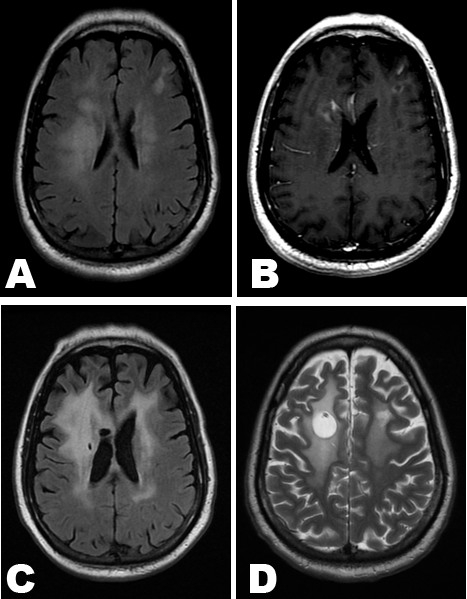

A 53-year-old immunocompetent male presented with tremor involving both hands for four months. His clinical conditions deteriorated for the subsequent two months when he had difficulties in caring for himself. He was found to have left-sided weakness during physical examination. A brain magnetic resonance imaging (MRI) scan showed patchy confluent hyperintensity on axial T2-weighted sequences in the deep and subcortical white matter of both cerebral hemispheres (Figure 1A). The T1-weighted gadolinium-enhanced images showed enhancement in bilateral frontal areas (Figure 1B). Analysis of cerebral spinal fluid (CSF) showed slightly increased protein level (67 mg/dL) while glucose level was normal. Cytology did not reveal malignancy. CSF examinations for Cryptococcus, CMV, Enterovirus, HSV, multiple sclerosis panel, Purkinje cell antibody and AFB cultures were all negative. Tests for syphilis, Borrelia burgdorferi, JC virus, copper and mercury levels, myasthenia gravis, and FMR1 gene mutation were either negative or normal. Electroencephalogram showed no epileptiform activity. MRI of cervical, thoracic and lumbar spine was unremarkable, as was CT of the chest, abdomen and pelvis. Cerebral angiogram and ocular slit lamp examination were normal. Although a brain biopsy was recommended, the patient and his family did not consider it initially. For the subsequent two months, he became bed-bound and confused. A repeat MRI scan showed the enhancement in the left frontal lobe increased in size with more surrounding edema. There was progression of patchy and nodular foci of contrast enhancement in the basal ganglia, upper brainstem and dentate nuclei in the cerebellum. He received empiric treatments with high dose methylprednisolone and plasmapheresis. Steroids improved his leg strength albeit the effect was short-lived. Plasmapheresis offered no benefit. Eventually, the family consented to a biopsy. The lesion in the left front lobe was biopsied. The pathology revealed both CD-20 and CD-3 positive cells scattered in the brain parenchyma and in perivascular space as small aggregates. The B lymphocytes appeared large with irregular nuclear contours (Figure 2A). They stained positive for CD-20, MUM-1, BCL-2 and BCL-6 with an increased expression of Ki-67 by immunohistochemistry. Immunoglobulin gene rearrangement study of the brain biopsy demonstrated an isolated, prominent peak while T cell receptor gene analysis was negative. The results indicate that the B cells had a common clonal origin while T cells did not. Collectively, the evidences supported a diagnosis of LC. Thereafter, a scrotum ultrasound detected a solid mass in the right scrotum. A right inguinal orchiectomy confirmed a diagnosis of DLBCL (Figure 2B) which stained positive for CD-20, MUM-1, BCL-2, BCL-6 and Ki-67. A subsequent PET scan did not detect any abnormalities. His initial treatment involved two cycles of high dose methotrexate (6 g/m2), temozolomide, and one cycle of rituximab, cyclophosphamide, doxorubicin, vincristine and prednisone (R-CHOP). He did not have noticeable functional improvement. He was subsequently transferred to our clinic. The plan was to focus on LC initially by adding intrathecal therapy (IT). R-CHOP would not be used upfront as CHOP with high dose methotrexate had resulted in prolonged cytopenia. For systemic therapy, he was treated every two weeks using a regime similar to what was reported [4]. He received four cycles of high dose methotrexate (3 g/m2), vincristine, procarbazine and dexamethasone plus systemic rituximab, followed by two cycles of systemic cytarabine with rituximab. For IT, 12 mg of methotrexate and 16 mg of rituximab were given via Ommaya reservoir. IT was administered on fourth day of each cycle of systemic chemotherapy. The feasibility, safety and effectiveness of IT rituximab were previously described [5]. He responded to IT promptly. Following a second course of methotrexate and rituximab via Ommaya reservoir, he was able to wiggle his toes and raise his left foot, which he could not accomplish prior to IT. At the end of six cycles of systemic as well as intrathecal therapy, he no longer had hand tremor. He was able to sit up and ride in a wheelchair. He still could not stand on his own. His cognitive function also improved although he was slow in responding to simple questions. MRI scan at seventh month of treatment showed resolution of abnormal enhancement in bilateral cerebral hemispheres. However, the diffuse white matter hyperintensity on T2-weighted sequences still remained (Figure 1C).

Subsequently, the patient received weekly IT with methotrexate and rituximab for 16 weeks as an outpatient until he no longer needed ambulette transportation and could ride in a car. The treatment frequency was then reduced by 50% with methotrexate and rituximab on alternate weeks for another 16 weeks. When he was able to walk and ride a bicycle, the treatment frequency was reduced by another 50% for 8 more weeks. The treatment for his CNS disease lasted a total of 14 months. The only complication during outpatient IT was an encephaloclastic cyst [6] detected during a follow-up MRI towards the end of IT (Figure 1D). However, he has remained completely asymptomatic.

Cursor on image to zoom/Click text to open image

Figure 1: (A, B) Brain MRI scan at presentation. (A) Axial T2-weighted FLAIR image showing ill-defined hyperintensity in bilateral periventricular and subcortical regions with some mass effect, (B) On T1-weighted gadolinium-enhanced image, there are abnormally enhancing lesions in bilateral frontal lobes (arrows), (C) Brain MRI at seventh month of therapy. The T2-weighted FLAIR image demonstrates persistent hyperintensity in bilateral white matter, and (D) T2-weighted sequences of brain MRI towards the end of intrathecal therapy reveal a cystic change (arrow) around the Ommaya catheter.

One challenge in managing this case was to determine optimal treatment duration. The persistence of diffuse hyperintensity on T2-weighted MRI sequences (Figure 1C) even when his symptoms were improving made it hard to decide when to stop therapy. In the end, adjustment of IT regime in our case was based on functional improvement. During the 10 months of outpatient IT, the only complication was an encephaloclastic cyst. It was reported to be associated rarely with IT methotrexate or topotecan [6] [9]. Its formation, as hypothesized, is due to back flow of chemotherapeutic agents and local chemical encephalitis. In our case, the cyst did not cause symptoms as reported [6] [9] nor did it resolve after IT was discontinued for a long time [9].